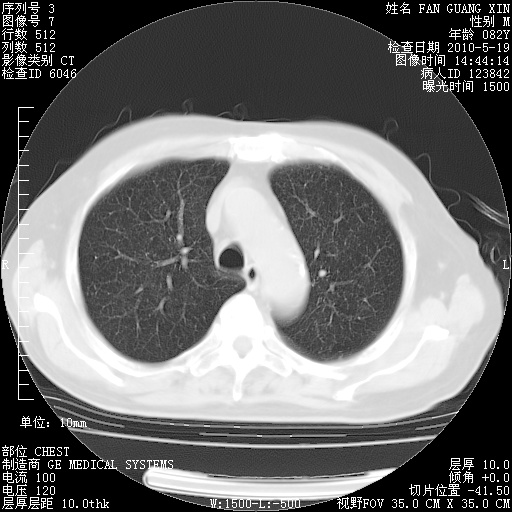

复查肺部CT,明显好转。为什么发热呢?

治疗3周后的肺部CT

治疗3周后的肺部CT纵隔窗